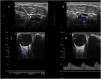

This is the case of a patient with complete occlusion of the internal carotid artery (Fig. 1A and B, arrows). A Doppler study using a transorbital approach of the ipsilateral ophthalmic artery reveals the presence of reversed Flow because the ophthalmic artery is being filled through naso-angular anastomosis where the external carotid artery meets the branches of the internal carotid artery via the facial artery nasal branch that anastomoses with the orbital branch of the ophthalmic artery (Fig. 1C). The Doppler ultrasound of the contralateral ophthalmic artery (Fig. 1D) reveals a positive flow for comparison purposes. Flow reversal in the ophthalmic artery is a specific ultrasound sign of critical or complete occlusion of the ipsilateral internal carotid artery.